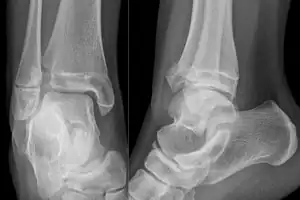

| X-ray of a Tillaux fracture in an 11 year old female | |

- X-ray ( Anteroposterior, lateral, and Mortise views)